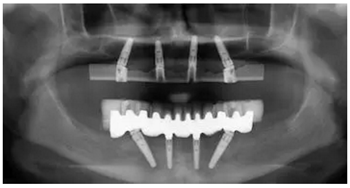

手術(shù)后90天拍攝連帶內(nèi)錐形連接愈合基臺(tái)的X光片。

手術(shù)后16周最終修復(fù)X光片:計(jì)算機(jī)輔助導(dǎo)板引導(dǎo)種植能夠保證在All-on-4治療中精準(zhǔn)安全地植入軸向和傾斜植體。